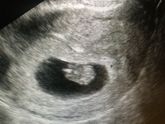

Растём потихоньку

Я чувствую себя самой счастливой, потому что я скоро буду мамой. Я 10 лет не могла забеременеть после моей первой беременности и к сожалению случился выкидыш.

Но сейчас во мне новая жизнь. За это время я многое взвесила, от многого … Читать далее